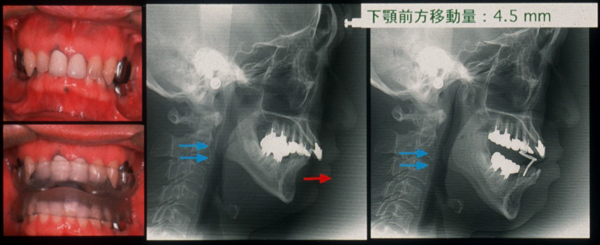

- 歯科装置:睡眠時に専用のマウスピースで下あごを数㎜前に引き出すことで、気道が潰れるのを防止する。

- CPAP治療:病院で、無呼吸を抑える圧力を調整し、自宅で睡眠時に用いる。機内のメモリーに睡眠時の呼吸の状況が記録されるので、経過の診療を確実。

健常者 睡眠時無呼吸 CPAP治療